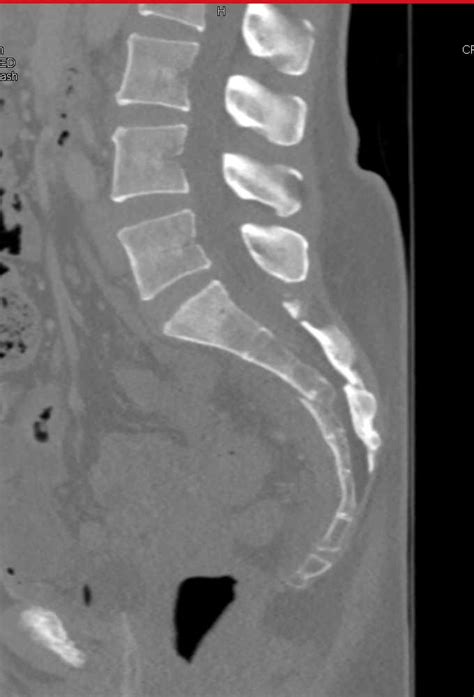

Sacral insufficiency fractures usually are parallel to the spine. A paradoxic inlet view of the upper sacrum on the anteroposterior plain pelvic radiograph heralds the diagnosis.

These sacral fractures are rare and occur after significant spinal axial loading. Sacral fractures are classified into three zones, zone 1, zone 2, and zone 3. A fracture involving the sacrum, a structure located at the base of the lumbar spine formed by the fusion of five sacral vertebrae. There are several classification systems for sacral fractures, but the most commonly employed are the denis classification and subclassification systems, and the isler classification system. Sacral fragility fractures cause significant pain and morbidity in the elderly population in which they occur. These sacral fractures are rare and occur after significant spinal axial loading. Possible causes, signs and symptoms, standard treatment options and means of care and support. Sacral fractures and injuries to the cauda equine. Fractures of the pelvis include sacral fractures which can vary. Login to view community videos. Plain radiographic, scintigraphic, ct, and mr imaging findings have been. Sacral insufficiency fractures in the elderly. Due to the complex nature of the injuries surgical therapeutic options are still being debated. This case was sent to me for my opinion on what to do. Sacral fractures are a common yet underdiagnosed cause of low back pain, predominantly in elderly women with osteoporosis. Ebraheim's educational animated video describes the classifications of sacral fractures. This injury is easily missed and the diagnosis is often delayed as it is difficult to detect on the anteroposterior view of the pelvic radiograph.